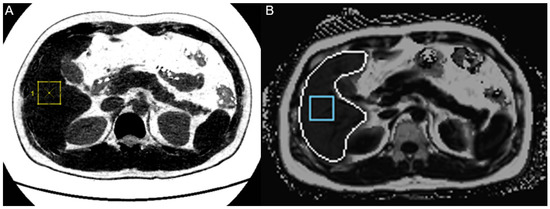

1. Introduction

2. Materials and Methods

2.2.2. MRI-PDFF